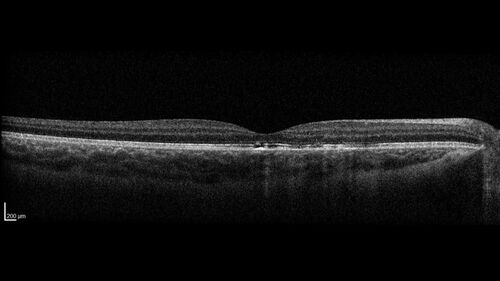

Laser pointer maculopathy

11 year old male When school started the patient noticed that he was having trouble reading and seeing out of both eyes. There are no retinal diseases in the family.

VA OD: sc20/25

VA OS: sc20/40

TP: OD:19 OS:18